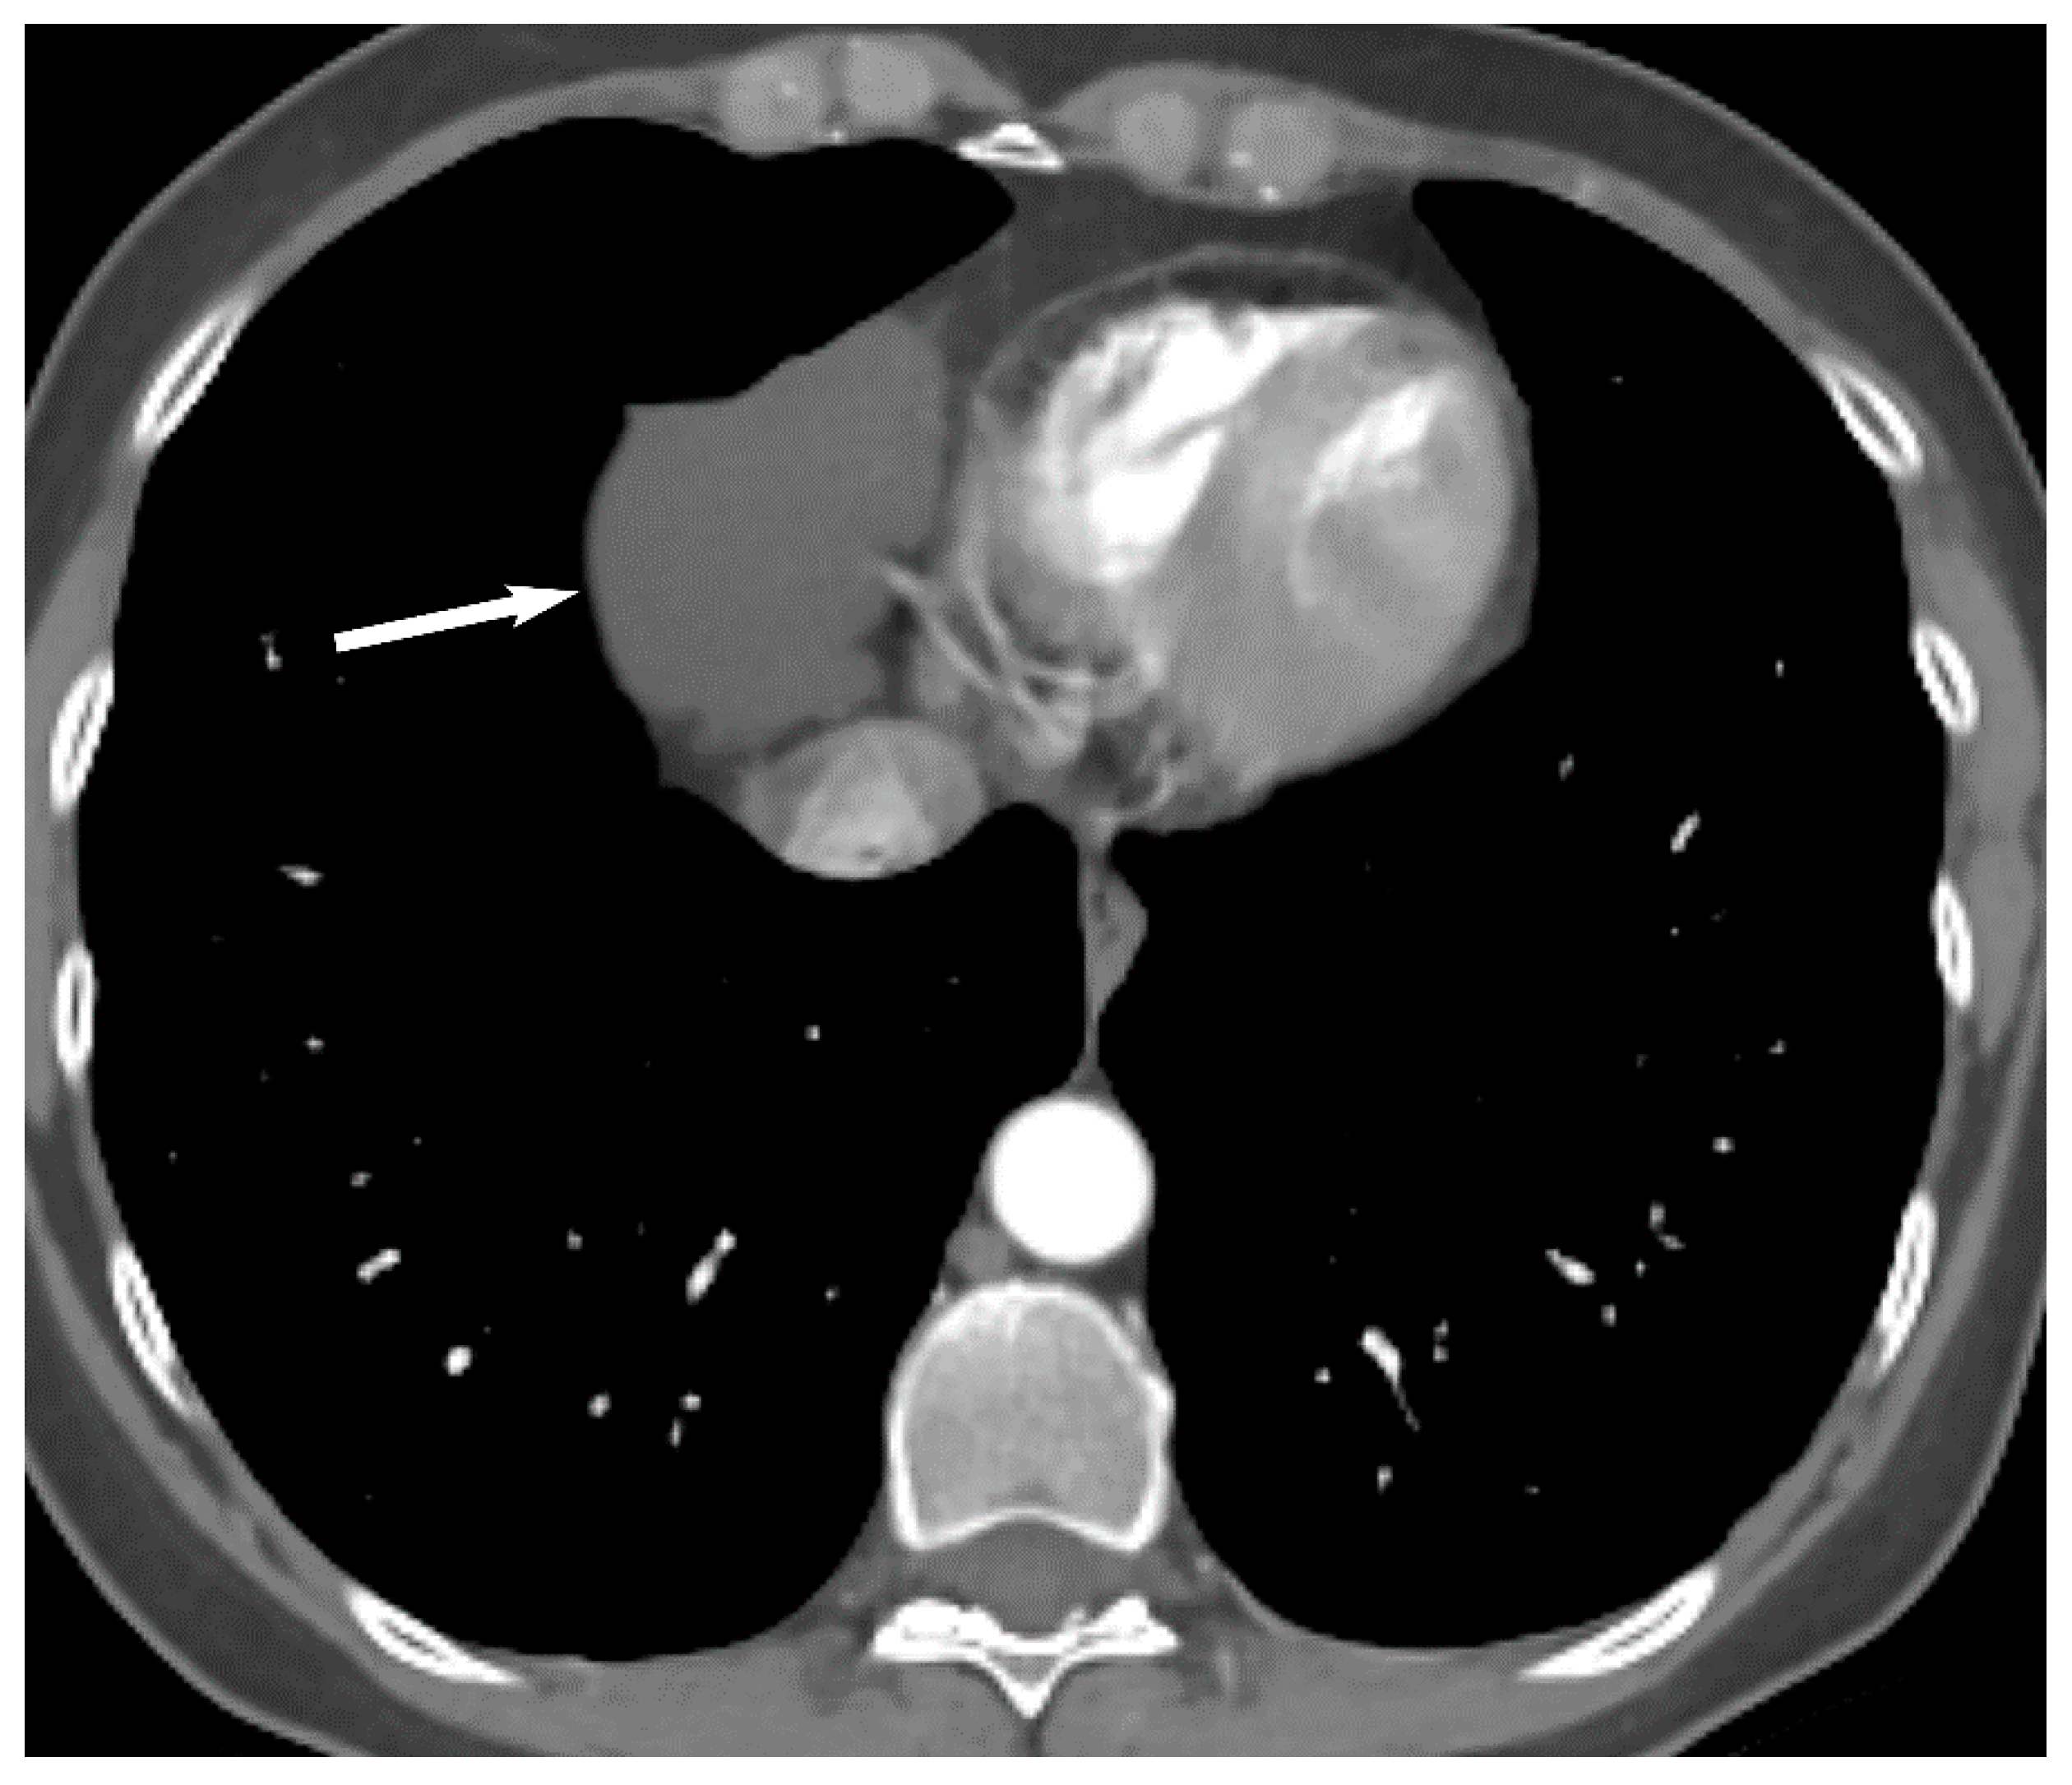

9. Hypervascular Lesions

7. Germ Cell Tumors